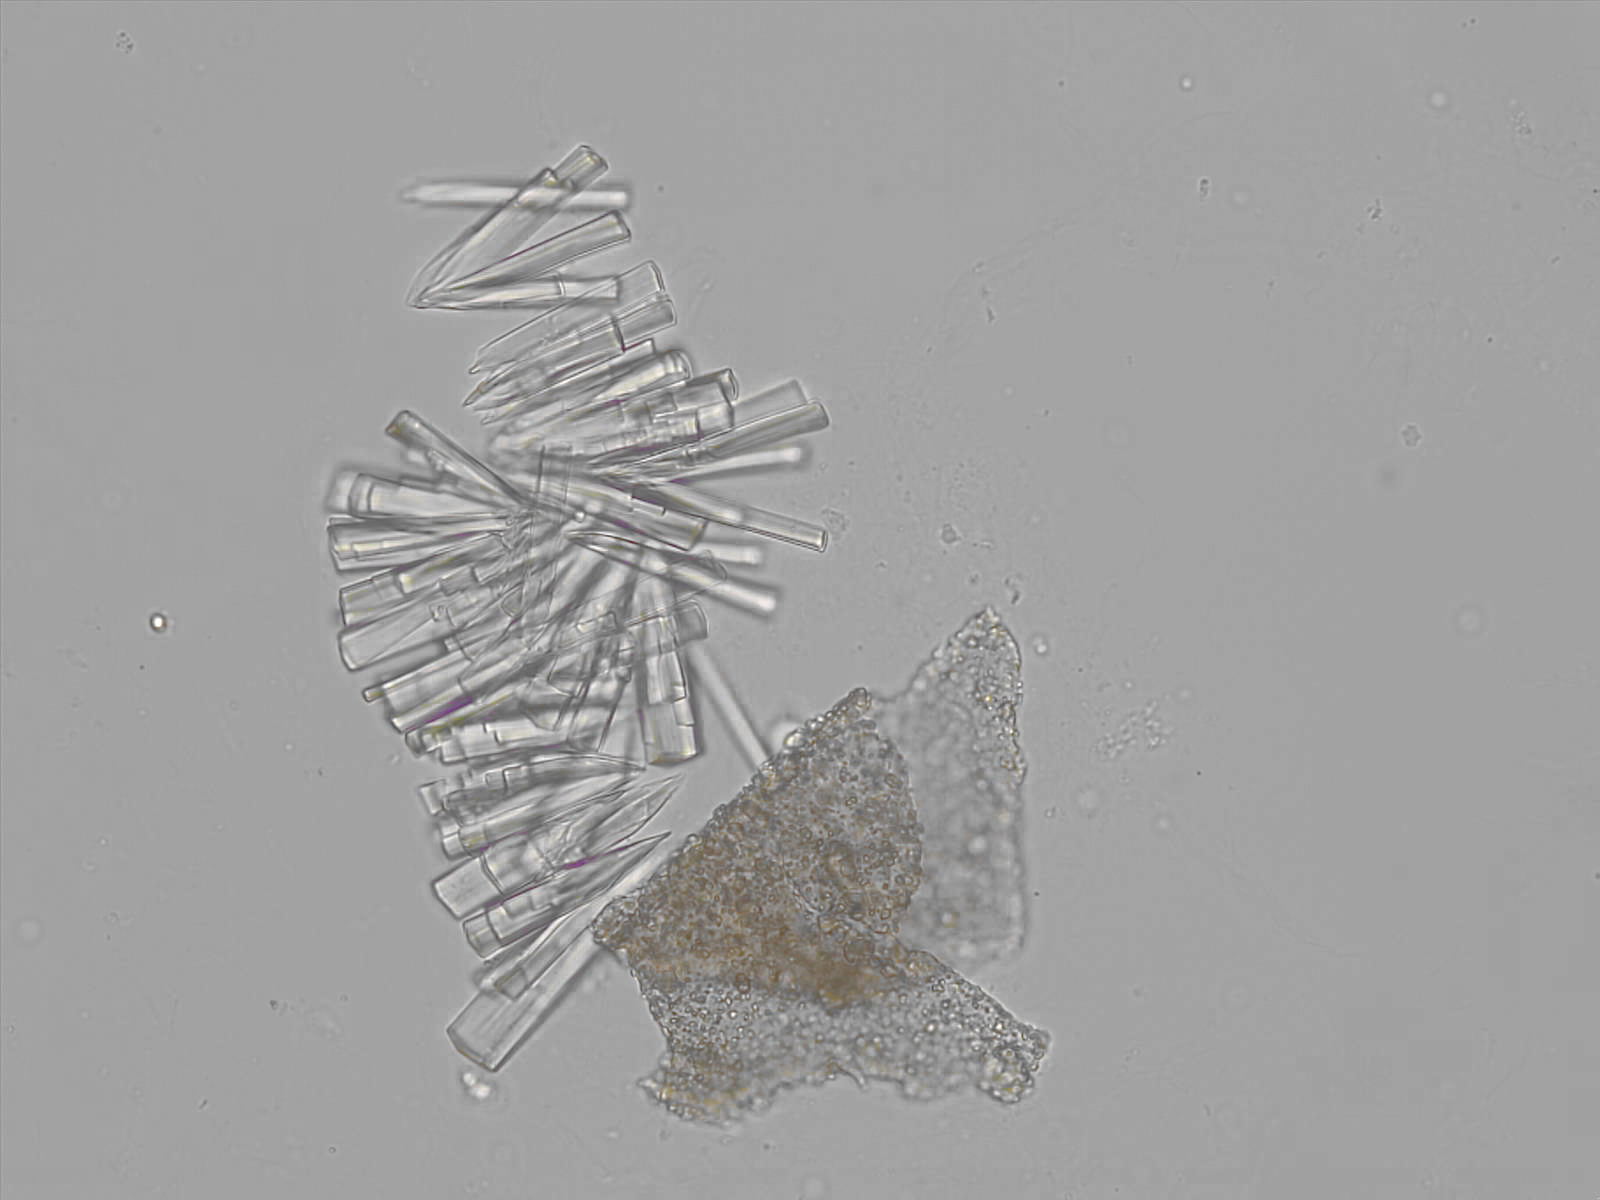

Calcium phosphate - Wedge form

Synonyms: Brushite, CaHPO₄·2H₂O

Calcium phosphate crystals frequently occur in normal urine with an alkaline pH (>7.0), but are also seen in people who form kidney stones. They are colorless and show great morphological variation. The crystals may occur as prismatic shapes, needle or wedge-shaped rods with usually blunt ends, and sometimes as star-shaped clusters (rosettes). These shapes are usually strongly birefringent. In addition, large, flat plates with irregular edges and granular structure can also be found. However, these plates are not birefringent.

Wedge-shaped calcium phosphate crystals may resemble crystals of uric acid, but the distinction can be made on the basis of the urinary pH (acidic in uric acid, basic in calcium phosphate) and the optical behavior under polarized light: uric acid crystals are birefringent, calcium phosphate sheets usually are not.